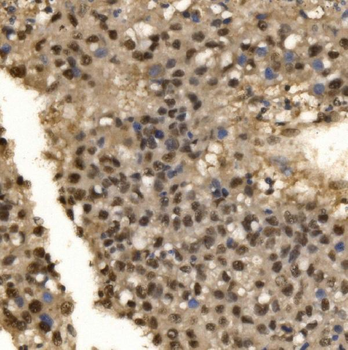

50 μl, 100 μl - MARK3 Recombinant Rabbit Monoclonal Antibody [orb704310]Featured

ICC, IF, IHC-Fr, IHC-P

Human, Mouse

Rat

Rabbit

Recombinant

Unconjugated

50 μl, 100 μl - Featured